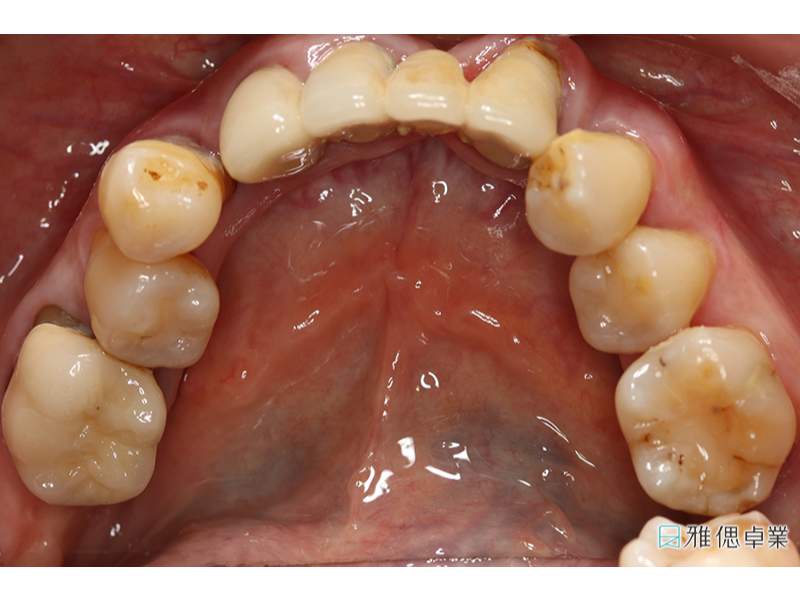

假牙模型上顎

假牙模型下顎

All on 6正式假牙(上顎)

All on 6正式假牙(下顎)